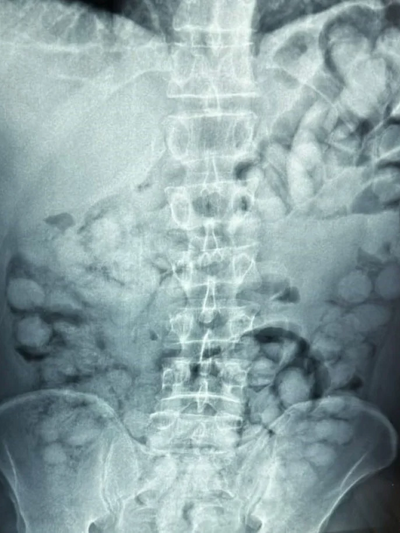

Ένας άνδρας, από τη Βραζιλία, συνελήφθη σήμερα το πρωί στο αεροδρόμιο «Ελ. Βενιζέλος», κατηγορούμενος ότι είχε καταπιεί σημαντική ποσότητα κοκαΐνης

Σύμφωνα με την ΕΛΑΣ, ο άνδρας έφτασε στην Αθήνα, μέσω Παρισιού και στον έλεγχο που διενεργήθηκε, διαπιστώθηκε ότι είχε καταπιεί περίπου 100 συσκευασίες κοκαΐνης.